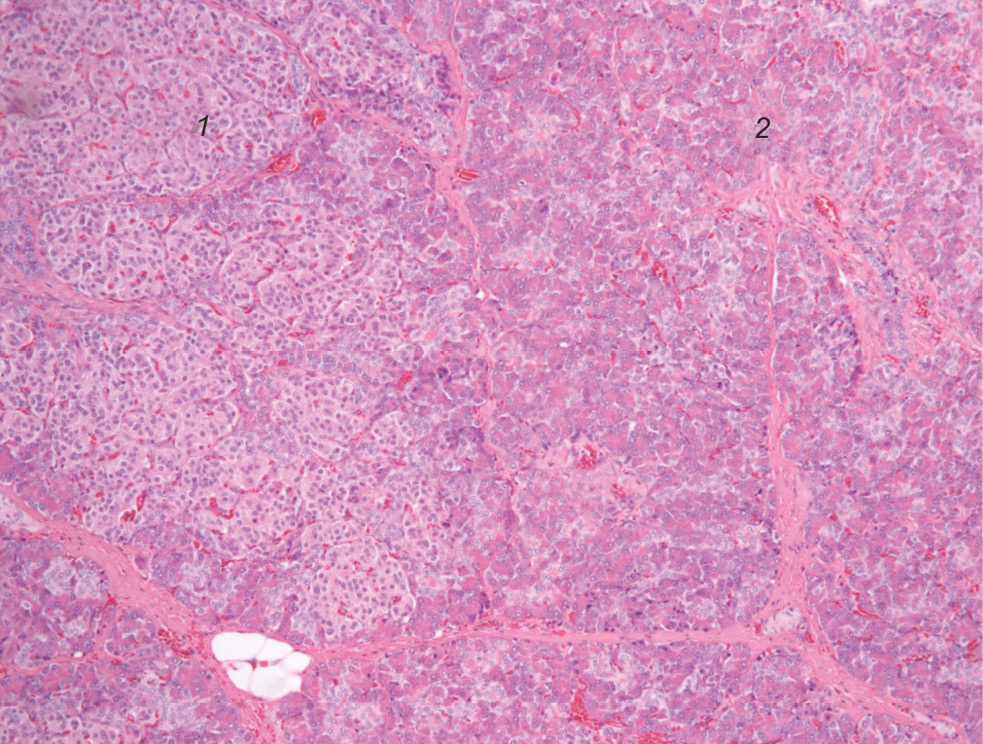

По данным экспресс-биопсии подтвержден патологический аденоматозный характер этого участка железы, окруженный тканью типового гистологического строения (рис. 4). На границе тела и хвоста железы, где пальпаторно определялся переход более плотной ткани в обычную, взят полнослойный биоптат, в котором подтверждено наличие нормальной ткани железы. На основании этих данных была произведена проксимальная гемипанкреатэктомия (тотальная резекция головки и тела железы) (рис. 5). Оставшийся участок хвоста — 3 × 1,5 см. Для обеспечения нормального функционирования оставшегося участка железы был создан панкреатоеюноанастомоз по Ру (рис. 6). Окончательное гистологическое исследование по залитым препаратам подтвердило аденоматозный характер поражения (рис. 7).

Рис. 4. Интраоперационная гистологическая картина: зона аденоматозной гиперплазии с увеличенными в размерах ядрами эндокриноцитов (1), окруженная тканью поджелудочной железы типового гистологического строения (2). Окрашивание гематоксилин и эозином, увеличение ×100

Fig. 4. Intraoperative histological picture: a zone of adenomatous hyperplasia with enlarged nuclei of endocrinocytes (1), surrounded by pancreatic tissue of a typical histological structure (2). Staining with hematoxylin-eosin, magnification ×100

Рис. 7. Гистологическая картина при осмотре залитых препаратов: аденоматозное поражение (1) без капсулы с тканью железы типового строения (2). Окрашивание гематоксилином и эозином, увеличение ×100

Fig. 7. The histological picture when examining the “flooded” preparations: adenomatous lesion (1) without a capsule with a typical gland tissue (2). Staining with hematoxylin-eosin, magnification ×100